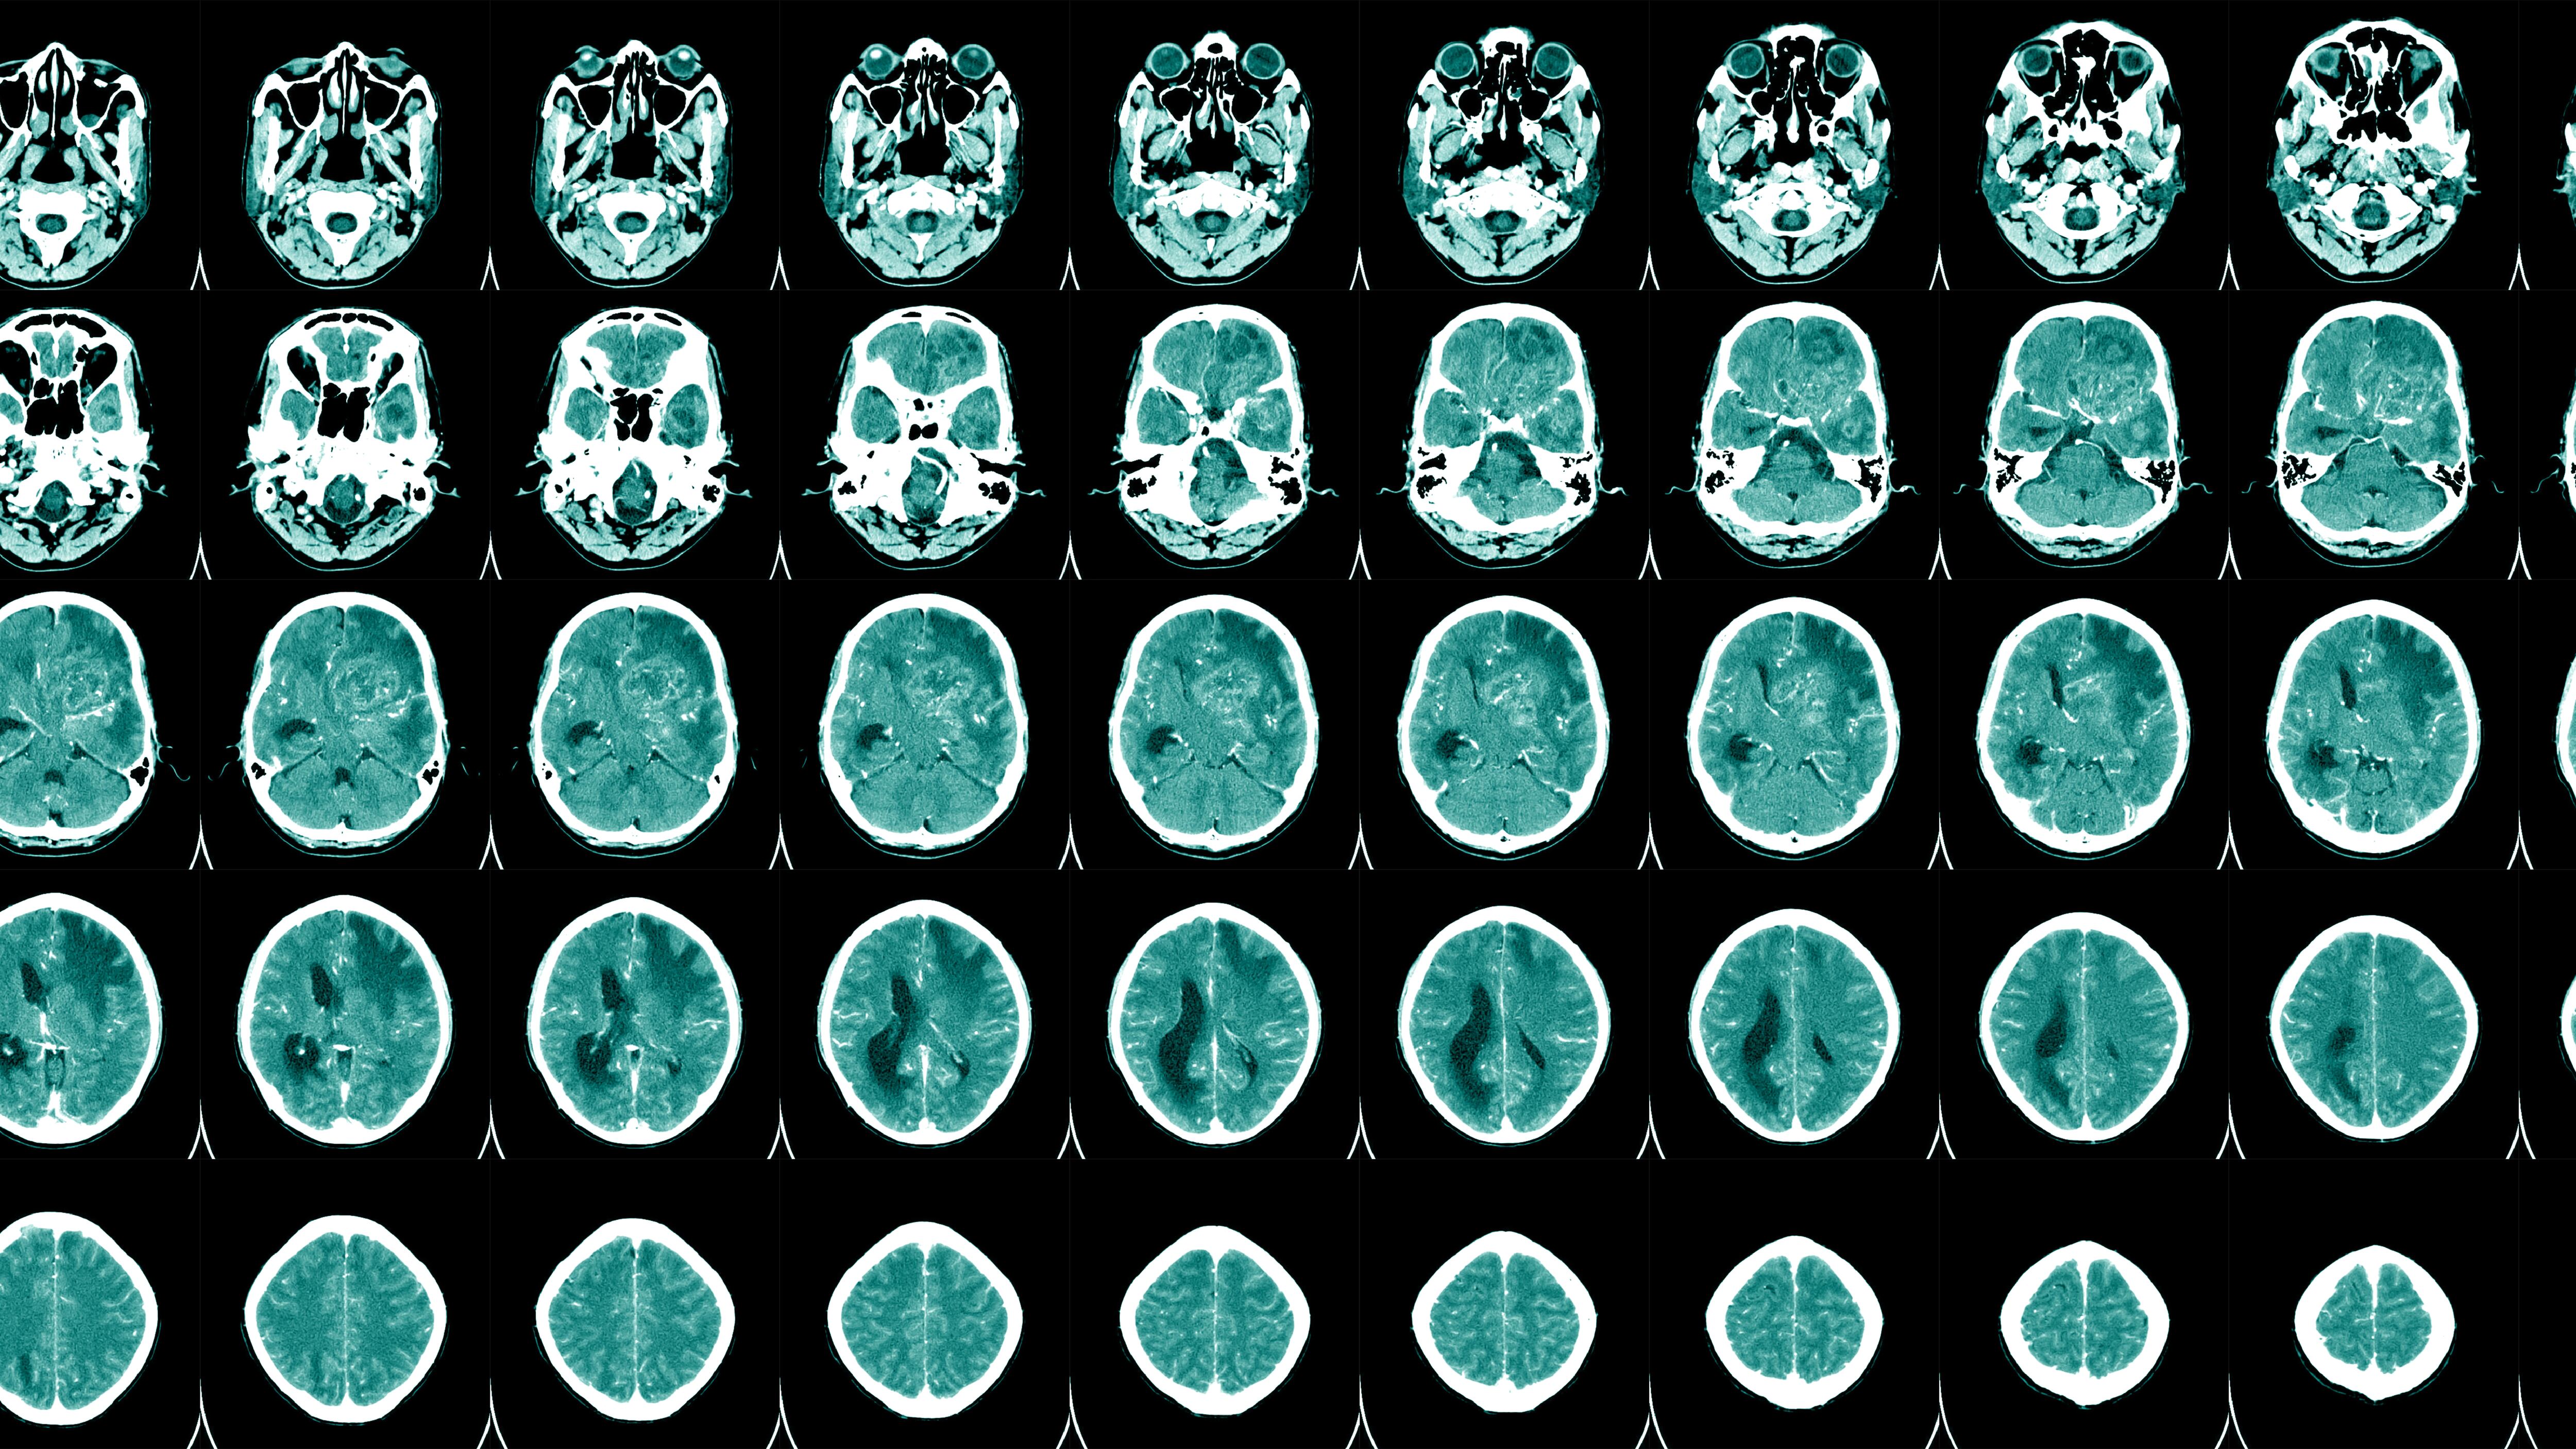

Understanding aphasia File photo. Aphasia is a language disorder frequently resulting from damage to the brain. (Tonpor Kasa/Getty Images/iStockphoto)

Aphasia is a disorder that results in loss of language, usually due to damage to the parts of the brain responsible for language.